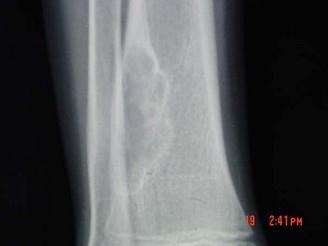

问题 男,30岁,感右小腿下段稍肿,其他无特殊,请结合所提供的图像,选择最佳选项 ( )

选项 A、良性骨肿瘤 B、纤维性骨皮质缺损 C、非骨化性骨纤维瘤 D、骨囊肿 E、骨结核

答案 C